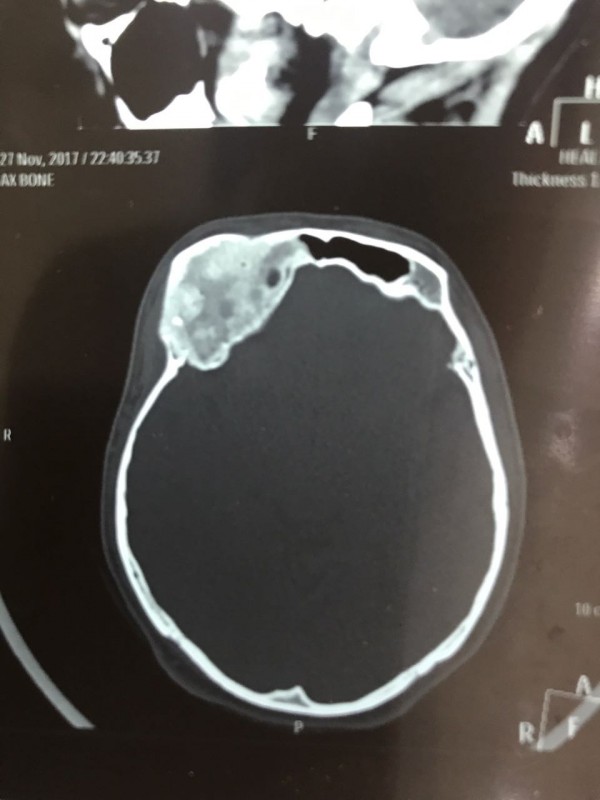

Как рассказал врач-нейрохирург городской клинической больницы № 7 Алматы Константин Ли, предварительный диагноз пациента - "фиброзная дисплазия лобной кости справа", то есть опухолевое поражение костей черепа. По его словам, сложность и уникальность операции в том, что опухоль плотно соприкасалась со зрительным нервом.

"Компьютерная томография показала, что костная опухоль поражала лобную кость и "крышу" орбиты глаза, которая, в свою очередь, сдавливала глазное яблоко. Чтобы убрать опухоль, потребовалось немало времени. Наша задача была сохранить глазное яблоко, зрительный нерв и сосуды. Если неправильно провести операцию и неправильно закрыть дефект, то в последующем это может привести к эстетической неполноте и асимметрии лица. Уникальность еще и в том, что в операции применялась 3D-стереолитография, которая делается только в Алматы", - рассказал он.

Снимок черепа. Опухоль с левой стороны. Фото предоставлено Константином Ли

Снимок сделан до операции. Фото предоставлено Константином Ли